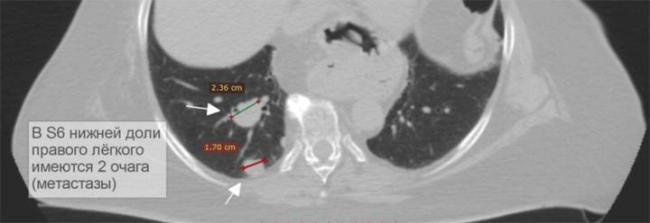

- Периваскулярные очаги – это патологические образования, которые находятся в непосредственной близости от кровеносных сосудов. Такое состояние наблюдается при онкологических патологиях и туберкулёзе. Очаги могут быть как единичные, так и множественные.

Как выглядят метастазы в легком на КТ?

Метастазы в легких на КТ Лимфогенные метастазы легких на КТ выглядят как множественные мелкие диссеминированные очаги. Они расположены вдоль междольковых перегородок и плевры. Картина напоминает туберкулез и саркоидоз, и в этой связи часто требует уточнения.